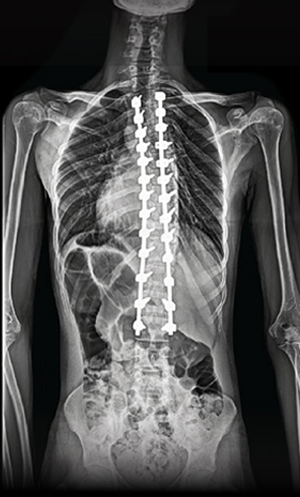

BEYOND RECOVERY : REAL STORIES

Gallery : Before - After